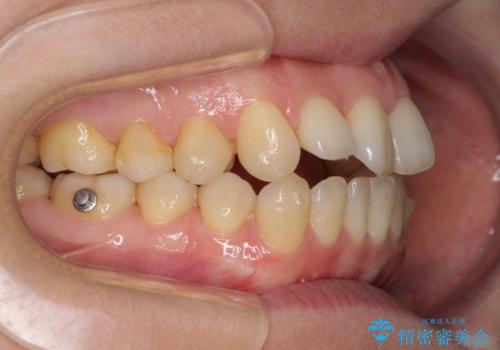

前歯の叢生とオープンバイト インビザラインでの矯正治療

- 前歯の開咬を気にして来院された患者様です。

開咬の治療は、前歯を閉じるように動かすとともに、上下臼歯を圧下(骨内にめり込ませる)させることで進めて行きます。

インビザラインは臼歯の圧下を効果的に行えるため、インビザラインを用いて矯正治療を行うこととしました。